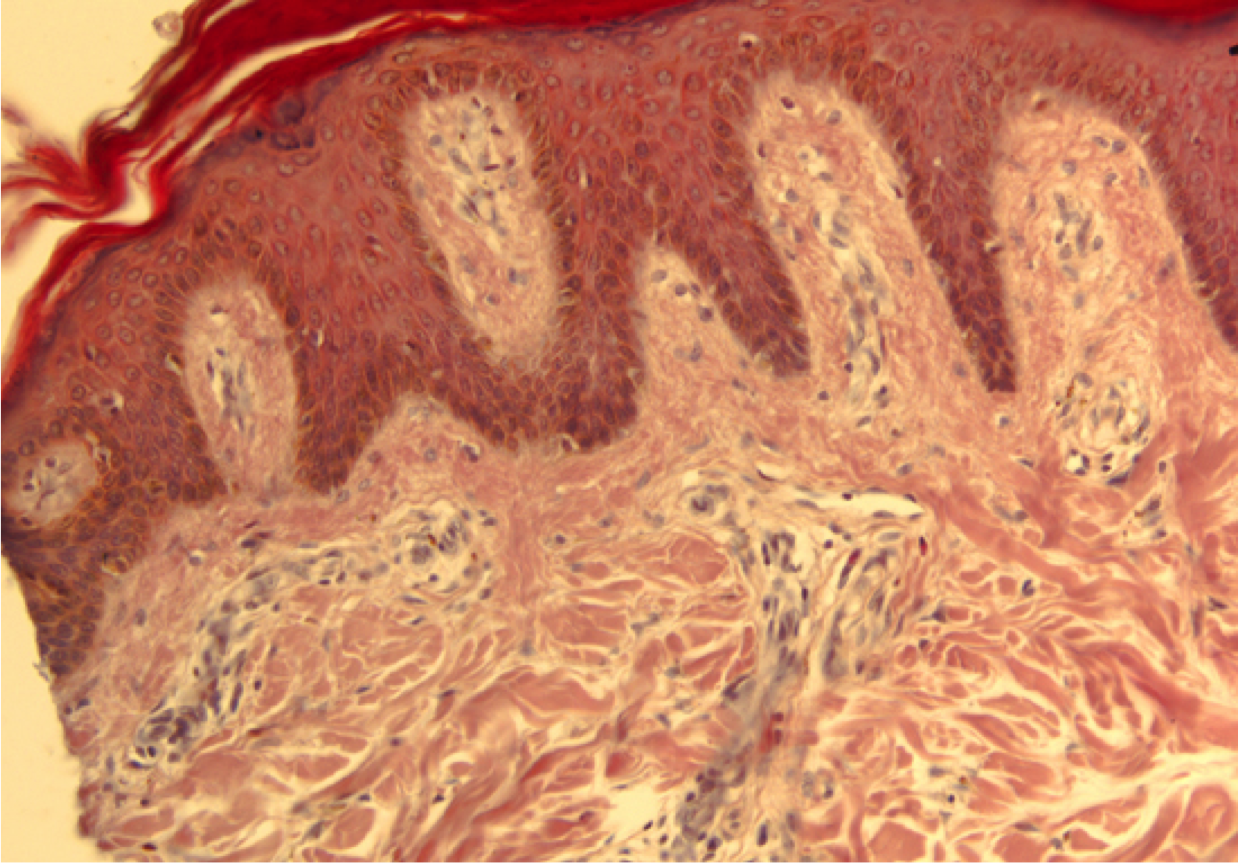

Identify

Elastic fibers stained in the dermis

Elastin and fibrillin make 0.1 to 10 micron diameter fibers

*Marfan’s syndrome - mutant fibrillin

Stains pink in H&E, but not distinguishable from other collagen fibers without Resourcin-fuchsin or Picro-Orecin stain